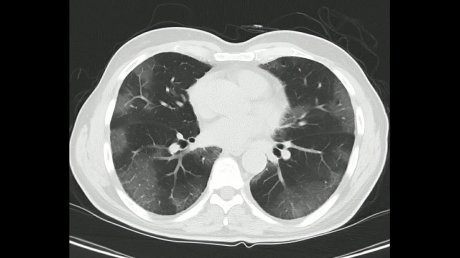

Ukoliko imate bilo koji od navedenih simptoma, pored testa na koronu, lekar će vas uputiti i na rendgen pluća, a u nekim situacijama i na skener (CT) grudnog koša. Na rendgenu se vide jasne „senke“ u zahvaćenim delovima, često obostrano. Na CT-u se, ukoliko je u pitanju pneumonija izazvana korona virusom, vidi slika „mlečnog stakla“.

CT grudnog koša - Corona CT grudnog koša - slika "mlečnog stakla" Foto: Shutterstock